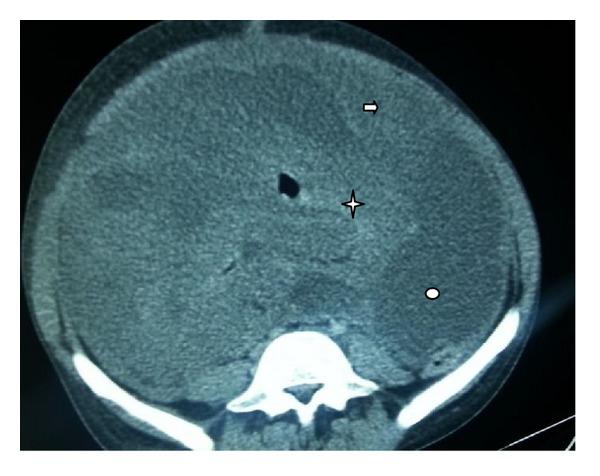

Malignant peripheral nerve sheath tumor of the small bowel is an extremely rare disease. Histologic distinction from other types of soft tissue sarcoma especially fibrosarcoma and leiomyosarcoma requires electron microscopy. Complete surgery remains the only curative treatment. However, late diagnosis makes curative surgery more difficult. The contribution of chemotherapy to incomplete surgery has been proved without controlled studies. We report a case of this type of lesion discovered following a small bowel perforation.